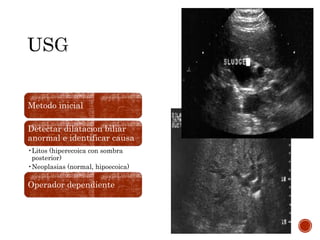

Metodo inicial

Detectar dilatacion biliar

anormal e identificar causa

•Litos (hiperecoica con sombra

posterior)

•Neoplasias (normal, hipoecoica)

Operador dependiente